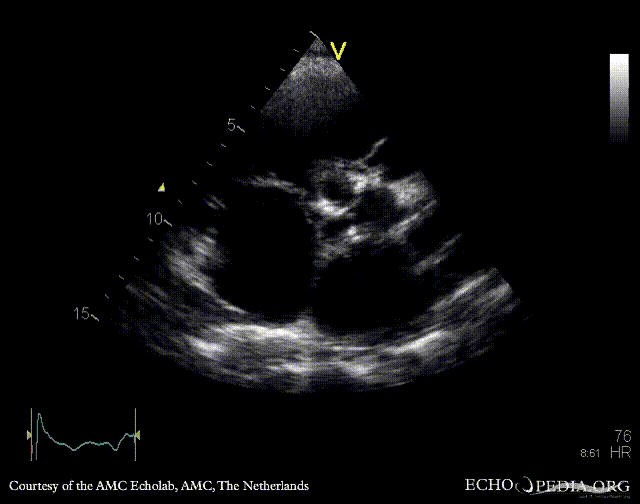

PSAX: thickend aortic valve PLAX: severe aortic and mitral regurgitation